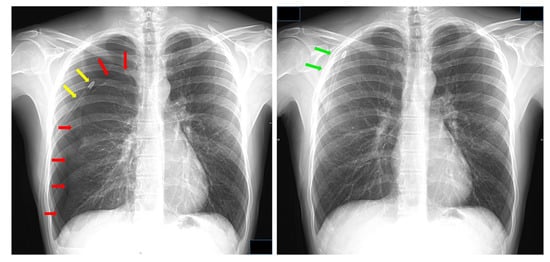

We believe that the effects of lung resection can be a direct function of the CDU used. For example, excessive build-up of negative intrapleural pressure can occur anytime we have a ‘stiff lung’, such as in patients with lung fibrosis [10] and in the acute phase after lung volume reduction surgery [11], or in the mechanically ventilated patient during and after extubation [12], when air leaks occur and an external source of vacuum is needed, [13] and whenever chest tube stripping is performed [14]. This, altogether, makes it important for a release technology to be built into the CDU we use. Some UWSD systems rely on breaking the water-seal to allow atmospheric air to backflow. Some authors have advised against this mechanism because air can be misinterpreted as persistent air leaks [15], to the point that ways have been developed to distinguish ‘true’ from ‘false’ air leaks [16]. We believe that the reverse air flow can actually be a safety feature, and that it does not set the stage for prolonged hospitalization as long as it is automatically regulated (Figure 2). The response time is crucial; indeed, when RAF occurs too early it leads to pneumothorax (Figure 7) whereas a delay in response generates a buildup of negative pressure which is clinically associated with discomfort and lung tears.

Figure 7.

(left) Pneumothorax induced by emptying the water contained in the water-seal reservoir in a compact UWSD (Rome by Eurosets). Red arrows: lung surface; yellow arrows: chest tube. (right) Pneumothorax resolved by switching to a dry-dry low-flow/low-pressure pump (Thopaz by Medela). Green arrows: lung surface. Data kindly provided by Dr. Alessandro Brunelli.